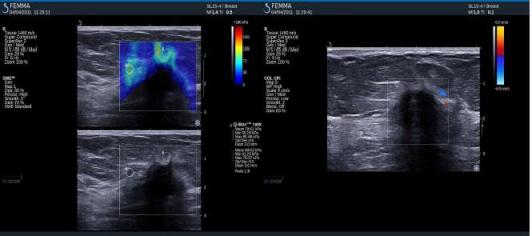

- výstupem elastografie je ultrazvukový B-obraz překrytý barevnou mapou. Každému bodu tkáně je přiřazena barva, která kóduje jeho elastické vlastnosti.

Barevné mapy v elastografickém obraze Modrá barva – měkká solidní tkáň (normální fibroglandulární tkáň), viskózní tekutina v cystách

Barevná škála – tuhá tkáň (maligní)

Černé výpadky – čistá tekutina (cysty) – příčné vlny se nešíří

– tuhá tkáň – příčné vlny jsou velmi slabé – jsou tlumeny, rychlá propagace příčných vln do okolí

Maligní tumor (IDC)

Pozitivní výsledky elastografie / histologicky potvrzená malignita

Invazivní duktální adenokarcinom